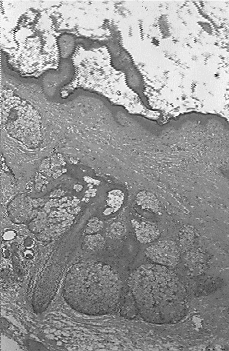

Se le practicó una laparotomía, encontrando un tumor redondeado en el seno de epiplón mayor, totalmente independiente de todas las estructuras vecinas, incluidos el útero y los ovarios, que eran de morfología normal. Se realizó omentectomía parcial, que incluía la masa, y se estudió peroperatoriamente. La pieza (Fig. 1) correspondía a un quiste de paredes calcificadas, de 12 x 7 cm, con abundantes pelos, material queratinoso, fragmentos óseos y dientes. El diagnóstico intraoperatorio fue de teratoma del omentum. En el estudio rutinario en parafina, se comprobó la existencia de epidermis con anejos cutáneos (Fig. 2), hueso y epitelio digestivo. No se identificó tejido neural. Así, el diagnóstico definitivo fue el de teratoma quístico maduro.

| Figura 2.Imagen histológica del mismo. Se observa epidermis con sus anejos. Hematoxilina-Eosina, 100 x. |